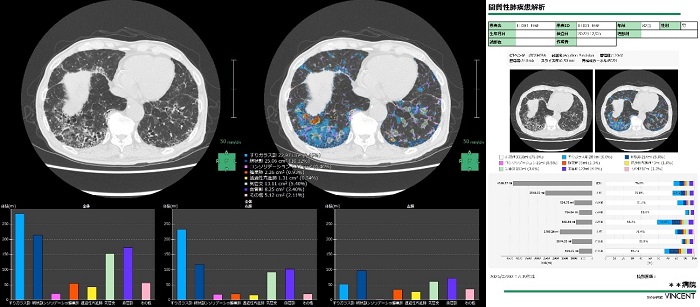

そのほか、脳区域解析や間質性肺疾患解析で、セグメンテーションした領域の定量化とレポート作成機能を新たに搭載した。正常脳と体積を比較する機能やアミロイドPET画像とのフュージョン時にSUVR(標準化取込値比)を自動算出する機能を備えており、その情報を自動でレポートに反映する。

間質性肺疾患解析では、CT画像から定量評価した結果をレポートとして出力する機能も追加した。システムは富士フイルムメディカル(東京・港区)が販売する。